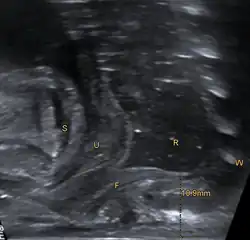

Nach der ersten Befunderhebung schließt sich eine perinaeale Sonographie zur Ermittlung der Distanz zwischen Rektumblindsack und Anus-Sollstelle sowie zum Ausschluss weiterer Fehlbildungen z. B. der Nieren und des Spinalkanals an.[2] Ein Fistelgang ist sonographisch in der Regel nicht darstellbar.[10]